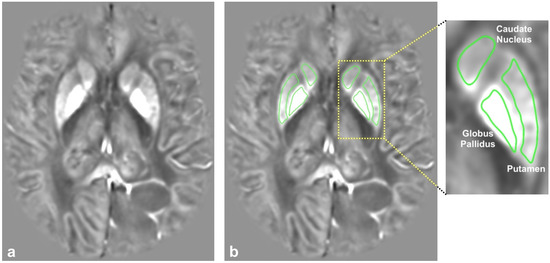

2. Materials and Methods